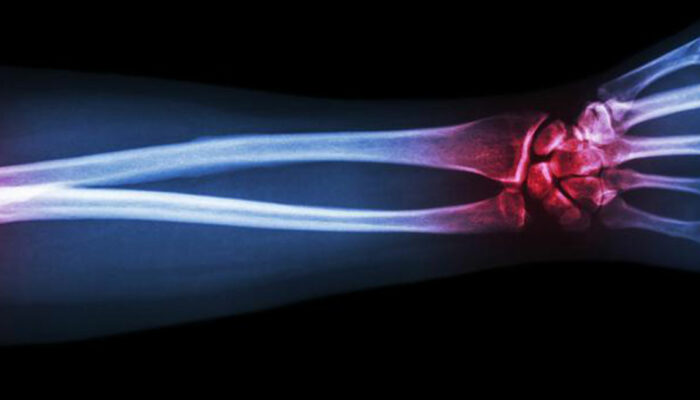

Gout is a type of arthritis that primarily attacks the joints and other body parts like the ears, wrists, knuckles, knee, ankles, and other small joints. It is often characterized by painful swelling, stiffness, and inflammation of these affected joints. The swelling and stiffness are mainly the results of excess levels of uric acid forming crystals in the joints. The pain is due to the inflammatory response to the crystals formed.

After doing a thorough physical exam, the doctor may also take a sample of the fluid from the swelling of the joint to look for uric acid crystals. A blood test is also needed to know the levels of uric acid in your bloodstream.